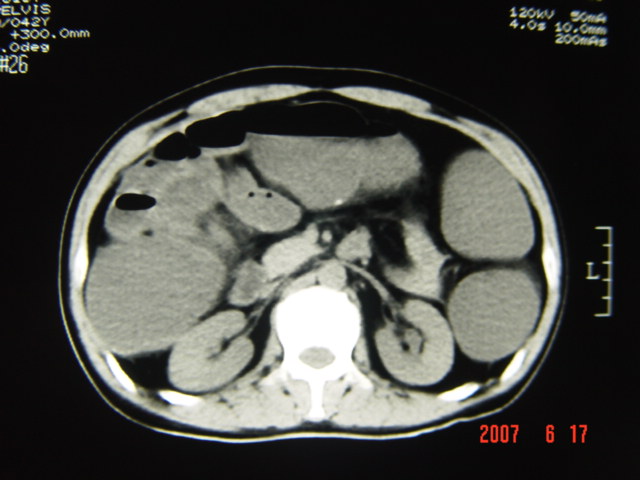

[br][br]以下是引用lkc8963在2007-6-17 13:32:00的发言:[br]完全支持邓主任意见:降/乙交界部占位性病变伴不全梗阻.做个增强或者be可能更好.